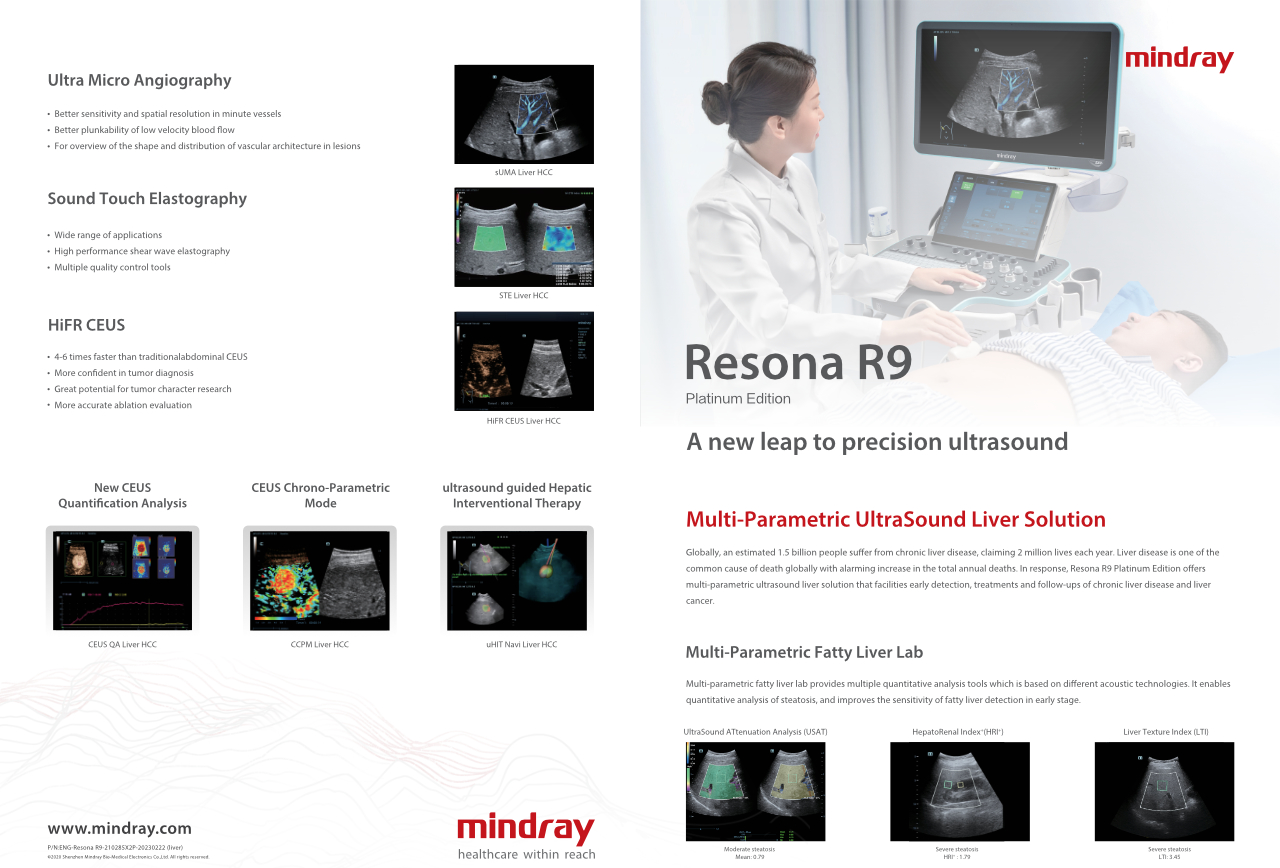

Quanto chiaramente puoi visualizzare il fegato?

Per le lesioni focali epatiche, come l'emangioma o il tumore al fegato, l'imaging di contrasto a ultrasuoni svolge un ruolo importante. La tecnologia di imaging di contrasto Ultra-wideband non-linear UWN+ consente di ottenere una migliore penetrazione, un rapporto contrasto-tessuto pi├╣ elevato con un indice meccanico pi├╣ basso e un'osservazione del tempo di perfusione pi├╣ lunga.